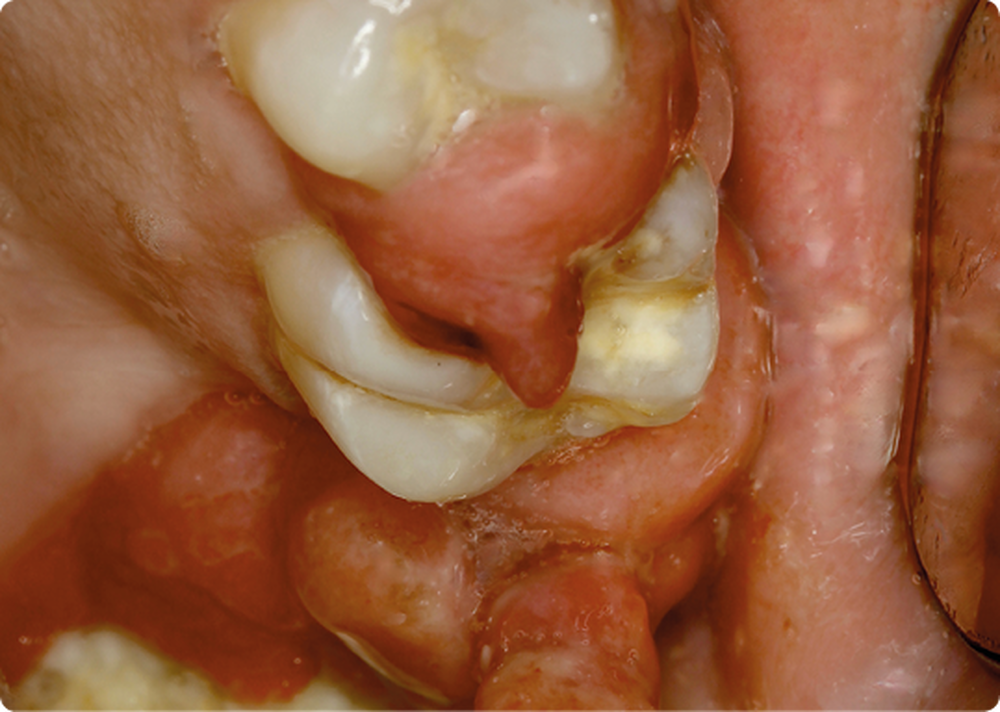

• On observait une hyperplasie gingivale intéressant les 4 régions molaire-prémolaire, avec des dents plus ou moins mobiles ; les secteurs antérieurs étaient épargnés. Cette hyperplasie gingivale était par endroits très volumineuse et prenait parfois l’aspect d’un granulome pyogénique.

• L’hyperplasie gingivale était revêtue par un épithélium malpighien kératinisé, irrégulier, comportant quelques ulcérations superficielles. Les crêtes épithéliales étaient par endroits discrètement hyperplasiques…